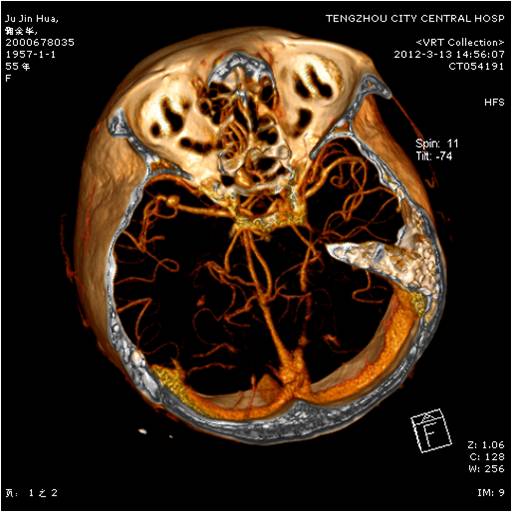

動脈瘤夾閉術前 動脈瘤夾閉術后